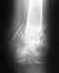

Полный вывих АКС, фиксация крючковидной пластиной.

Здравстуйте! Получил полный вывих АКС, при падении на плечо.

Диагноз был поставлен сразу же, при обращении, поставлен я думаю верно, отправили на операцию, предложили фиксацию спицами и лавсаном за клювовидный отросток либо крючковидной пластиной, объяснив что этот метод лучше по трудоемкости операции и жесткости фиксации. Я выбрал пластину, но мне пришлось ждать ее две недели, за это время у меня почти полностью востановилось функциональность руки, она уже почти не болела и двигалась в полном диапазоне, эфект клавиши почти отсутствовал, потому что ключица как-то приросла в вывихнутом состоянии. Однако косметический эффект не оставил мне никаких сомнений и меня прооперировали, поставили пластину, да так что она находится не строго на ключице паралельно полу, а сдвинута немного вперед, из-за этого получилось что прооперированная ключиться у меня находится гораздо ниже здоровой, опять же косметический дефект. Но слава богу прошел месяц после операции, рука потихоньку приходит в норму, однако все еще чувствует себя хуже и не дает двигаться в полном диапазоне движения, так как это было до операции, однако я думаю что это вопрос времени и с каждым днем мне становится все лучше и лучше. Но меня опять же напугал врач у которого я сейчас наблюдаюсь, пластину через год должны убрать, он сказал что когда ее уберут, ключится обратно выскочит в то состояние как до операции и надо оставлять пластину, но эту пластину оставлять нельзя, на ту, которую можно было бы оставить у меня не хватило денег.У меня такой вопрос, действительно ли когда уберут пластину, ключица встанет в состояние вывиха, если да, то зачем тогда нужна такая операция, после которой я после шва на плече кожу вообще не чувствую, нервы отсекли, кстати, тоже вопрос, востановиться ли чувствительность, если же ключица после удаления пластины останется в том положении как она сейчас, можно ли мне будет нагружать руку (я всетаки КМС по пауэрлифтингу и надеюсь продолжить) или при значительной нагрузке будет рецидив? Если нужны снимки, потом выложу, когда с больничного отпустят они в больнице в моей истории болезни.